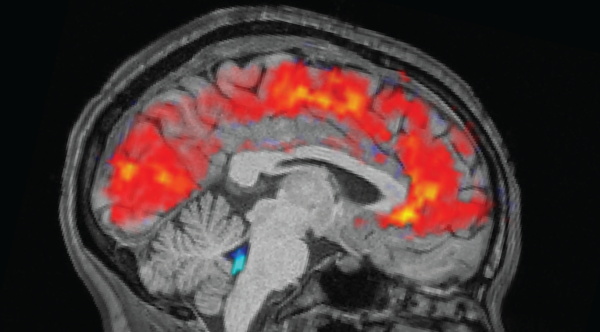

Researchers employed brain imaging to comprehend how cells are arranged to react to both known and unknown locations.(Image credit: Andrew Brookes/Getty Images)ShareShare by:

Fifty-six healthy participants, aged 20 to 37, were engaged and tasked with traversing a simulated realm within a scanner. Participants were instructed to navigate the virtual setting — a grassland encircled by peaks — whilst searching for six “objects” concealed throughout. Vatansever’s group used functional MRI, a method measuring cerebral blood flow, to track brain activity as the volunteers navigated across familiar and novel areas of this domain.

The research centered on the hippocampus, a cerebral region paramount for both memory and navigation. The hippocampus, resembling a seahorse, is abundant in place cells, which activate for particular locations. Prior studies indicate that one hippocampal end contains cells that trigger during consideration of general location, for instance, landmark placement in an adjacent urban center. Conversely, cells at the opposite end activate when contemplating specific sites, such as cereal box placement in one’s kitchen.

Positioned between the “beginning” and “end” of the hippocampus resides a gradient of activity uniting these broad and refined site depictions. Nevertheless, the cellular layout responding to a location’s novelty or acquaintance remained unexamined until now.

Vatansever’s cohort discovered that the head of the hippocampus held cells activating during participant explorations of prior locations. In contrast, cells at the tail were activated in new locales. Furthermore, the entire region exhibited a gradient pattern, transitioning from familiar to unfamiliar.

Different cerebral areas also showed varied responses to familiar and novel locations. The brain’s cortex — its advanced cognitive center — exhibited a cone-shaped gradient. “Centered within, segments indicate a ‘preference’ for acquaintance. As you move outward, there’s a heightened inclination to activate in response to novelty,” Vatansever clarified.